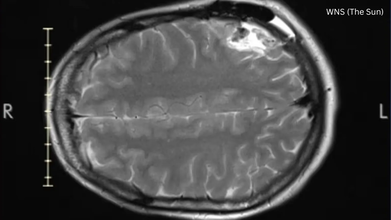

A study published in Frontiers in Aging Neurosciences people get older, the bone density in the lower back and thigh bone decreases significantly. This raises the risk of osteoporosis (OP). Therefore it becomes pivotal to pay early attention to nutrition, exercise ability, vitamin D levels, and uric acid levels in older individuals to prevent Ostreopsis and mitigate fall risks. The risk of falls and bone injuries among elderly individuals underscores the importance of preventive measures for maintaining bone health and minimizing fall risks.